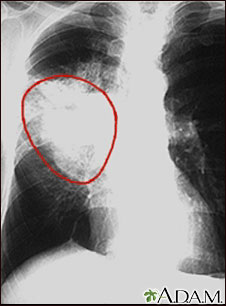

Lung cancer, frontal chest x-ray

A CXR in a patient with central cancer of the right lung. Notice the white mass in the middle portion of the right lung (seen on the left side of the picture).